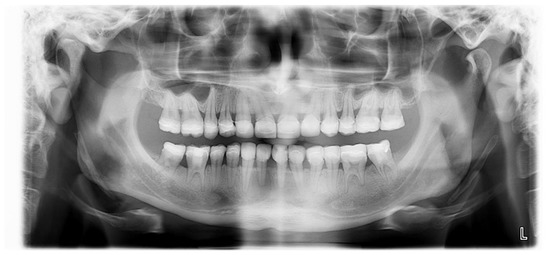

First, alginate impressions were made to obtain diagnostic casts. These casts were mounted in an articulator in order to analyze the case. Face photos and intraoral views were taken and are presented in Figure 1 and Figure 2. The orthopantomogram shown in Figure 3 was realized.

Figure 3.

Orthopantomogram of the patient’s initial dental condition in February 2021.

The radiological examination revealed voluminous dental pulps, apical root resorptions on the lower molars and the absence of the upper left third molar and the two lower third molars.